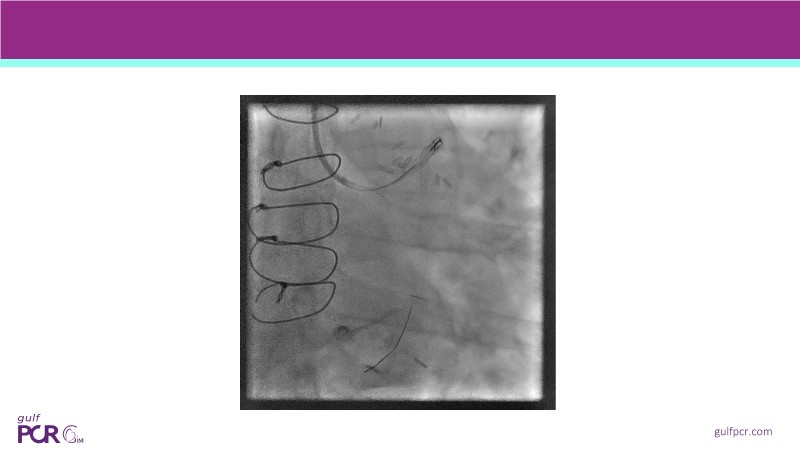

Calcified coronary lesions are a major challenge in PCI. This PCRGulf-GIM 2025 session showcases a complex case with intravascular imaging, highlighting how IVUS 123 guides each step.

From planning the procedure and understanding calcium distribution, to lesion preparation with modern modification tools, and post-PCI assessment to confirm stent expansion and detect complications, this session demonstrates practical, imaging-driven strategies.